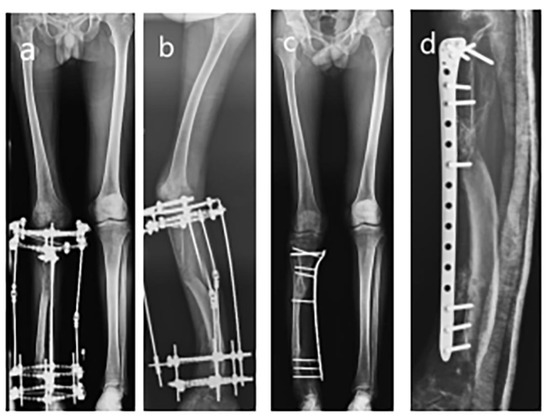

Figure 4.

The appearance of the lower extremity and removal of the plate. (a) The appearance of the lower extremities; (b) Flexion of the knee joint; (c) AP view full-length radiograph of lower extremities before plate removal; (d) Lateral view full-length radiograph of lower extremities before plate removal; (e) AP view full-length radiograph of lower extremities after plate removal; (f) AP view radiograph of tibia–fibula after plate removal; (g) Lateral view radiograph of tibia–fibula after plate removal.